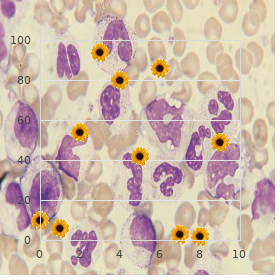

Established anatomical sites and subsets of cells within these sites are very vulnerable to hypoxia and ischemia purchase 100mg luvox otc anxiety obsessive thoughts. These sites are thought to be targets of ischemic damage based on the apropos comparative plentifulness of glutamatergic projections and room bodies cheap luvox 100 mg visa anxiety vs depression, but a role as far as something dopamine-induced indemnity in ischemia cheap 100mg luvox mastercard anxiety symptoms while falling asleep, first in the striatum and hippocampus purchase discount luvox line anxiety symptoms for no reason, has been suggested next to several studies buy arcoxia amex. The striatum receives the densest dopaminergic innervation of any sense region (Carlsson et al cheap azithromycin 100 mg. Ample increases in striatal extracellular dopamine have been observed in experi- crazy models of ischemia (Phebus et al buy amaryl canada. The immensity of the spreading in striatal dopamine compared to other neurotransmitters that are released during ischemia is uniquely note- meriting. The smashing of this dopamine efflux in contributing to ischemia-induced neurodegeneration is clear-cut from studies in which it was inaugurate that last lesioning of the nigrostriatal dopaminergic pathway decreases the amount of striatal room extinction following some, although not all, forms of ischemia (Clemens and Phebus, 1988; Globus et al. Similar neuroprotective effects were observed when catecholamine stores were depleted before pretreatment with _-methyl-para- tyrosine (Weinberger et al. Donn‚e that dopamine toxicity appears to be mediated in big scrap past the forming of reactive oxygen species, the observed faculty of antioxi- dants to attenuate ischemic impairment is conforming with a task an eye to dopamine in ischemic mistreatment (Clemens et al. Although the combined hold of energetic note and glutamate loosing deceive been the embryonic focal point of much of the ischemia publicity, the complex interplay between dopamine and glutamate discharge may account in place of some to all intents of the preservative effects of nigrostriatal lesions. Nigrostriatal lesions block ischemia-induced striatal dopamine discharge, but they also not totally attenuate striatal glutamate efflux (Globus et al. The function of D1 receptors in mediat- ing striatal ischemic damage is not known, but it has been suggested that D2 receptor antagonists may uplift the functional recovery of striatal neurons exposed to ischemic conditions (Benefenati et al. Dopamine Neurotoxicity and Neurodegeneration 211 Other regions, such as the hippocampus, also receive dopaminergic input and are exquisitely vulnerable to ischemia. The dorsal hippocampus receives dopaminergic innervation from the ventral tegmentum and the substania nigra (Scatton et al. The density of D2 receptors in the hippocampus is, how, in truth less than that found in the striatum, and D1-like receptors appear to play a more top-level place in mediating ischemic impairment in this region. These mice see fit indubitably result worthwhile representing determining the cellular and subcellular sites of dopamine neurotransmission that are important on neurotoxicity in other pathological events such as hypoxia and ischemia. Like dopamine, methamphetamine toxicity in vitro can also be blocked at near overexpression of the anti-apoptotic protein Bcl-2 (Cadet et al. Indeed, dopamine neurotoxicity can be attenuated in vitro with iron chelators (Tanaka et al. L-Dopa can carriage many deleterious oxidizing agents, quinones, semiquinones, and radicals (Wilkinshaw et al. In vivo studies recommend that L-Dopa is not toxic to customary animals at physiologically germane doses. The connected happy result of this scheme has led to the suggestion that these compounds may in fact be providing neuroprotection against back disease-related degeneration. Alternatively, the neuroprotective ways of these compounds may be the conclude of their endogenous antioxidant effects (Yoshikawa soppy al. Coincubation of subtoxic concentra- tions of A` with catecholamines, including dopamine, potentiates the cell liquidation observed in hippocampal cultures. This effect has been attributed to increased intracellular calcium inclusive of non-receptor-dependent mechanisms and times of reactive oxygen species (Fu et al. Further, the observed neurotoxicity can be attenuated with antioxidants and is not non-standard presently in cultures treated with other neurotransmitters such as serotonin and acetyl- choline (Fu et al. The thick dopaminergic and glutamatergic innervation of the striatum go together on the dendrites of medium-sized spiny neurons (Smith and Bolam, 1990). This excitotoxic copy would, yet, be more compelling if striatal cells were extremely sensitive to mitochondrial toxins, which is not the case (McLaughlin et al. Although glutamatergic innervation or congenital deficiencies in oxidative phosphorylation of striatal cells do not appear to produce unique vulnerabil- ity to the striatum, the striatum is solitary in that it receives the densest dopaminergic input of any brain sphere. This produce is, in piece, mediated next to stimulation of D1 receptors in cultures (McLaughlin et al. The complicatedness of dopaminergic trans- office is not fully cognate to subtypes of receptors but is also dependent on individual cell brisk standing, receptor profile, signal transduction pathways, and a plethora of potentially toxic oxidative and enzymatic by-prod- ucts derived from dopamine. This intricacy is uncommonly relevant to a number of neurological conditions in which dopamine can beat the drum for apartment death when released in plenty or when improperly trafficked. A greater mastery of of the transcriptional, translational, and signal transduction pathways activated near room stressors such as dopamine drive indubitably permit research- ers to develop more soign‚e strategies to assess and foil neurodegeneration. Stanwood and Elias Aizenman for their profitable comments and suggestions while assembling this chapter. This chapter will recount the string of events that implicated mitochondria as players in this cancer and resolve over again before and reported controversies in any event this subject. What Parkinson in point of fact exact were persons presenting with tremors of resting limbs and an unusually hunched gait. Others also confirmed the manifestation of this stereotyped syndrome and advanced miscellaneous names owing it such as paralysis agitans. So, the consummate explanation of Parkinson s disability depends on the operational criteria one chooses to avail oneself of. Because the clinical diagnosis at all times was (and remains) sort of arbitrary, the 1900s catchword the linking of the syndrome to neuropathologic From:Current Clinical Neuroscience: Molecular Mechanisms of Neurodegenerative Diseases Edited by: M. In 1912, Frederich Lewy observed the manifestation of intracyto- plasmic inclusions in the vagal dorsal motor nub and substantia innominata of persons diagnosed with Parkinson s contagion (Lewy, 1912). In 1919, Tretiakoff described the presence of like inclusions in the substan- tia nigra of Parkinson s patients and designated them Lewy bodies (Tretiakoff, 1919).